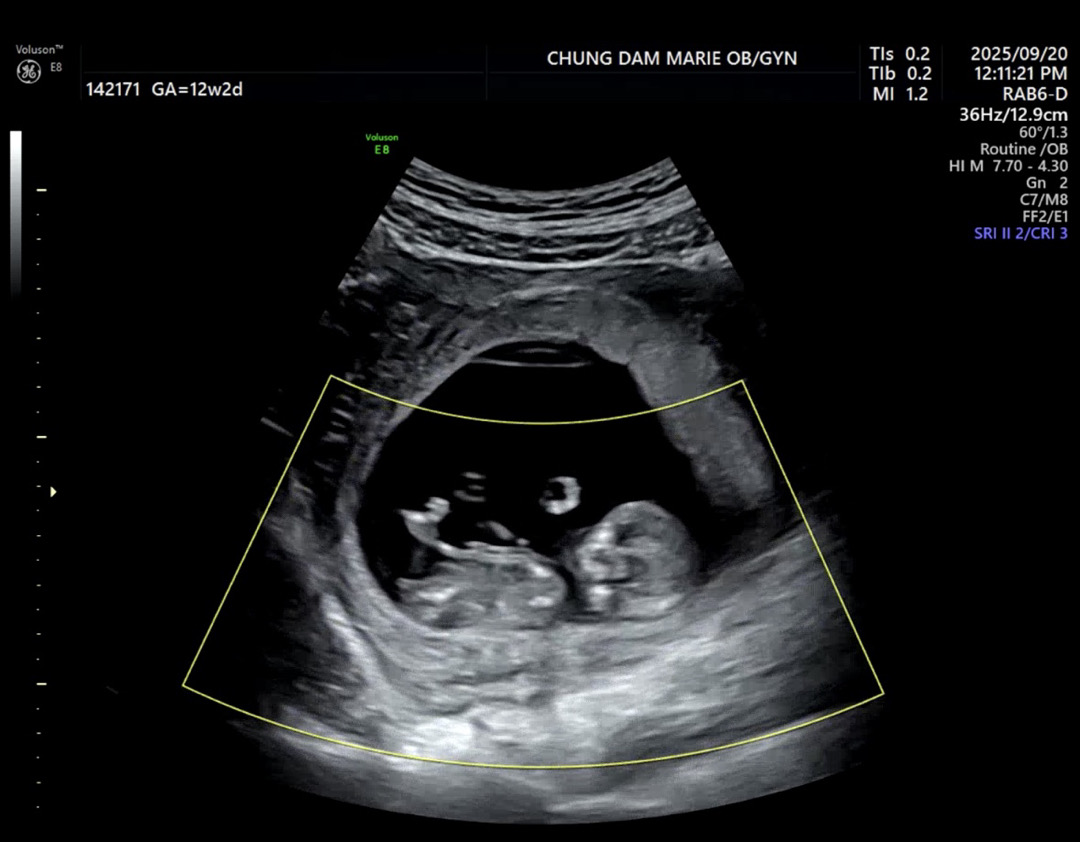

12주차 성별 각도법

성별이 너무너무 궁금해서…매일초음파 영상을 보고있어요.. ㅎㅎ남아로 보이시나요..? 여아로 보이시나요??? 조언 부탁드려요!